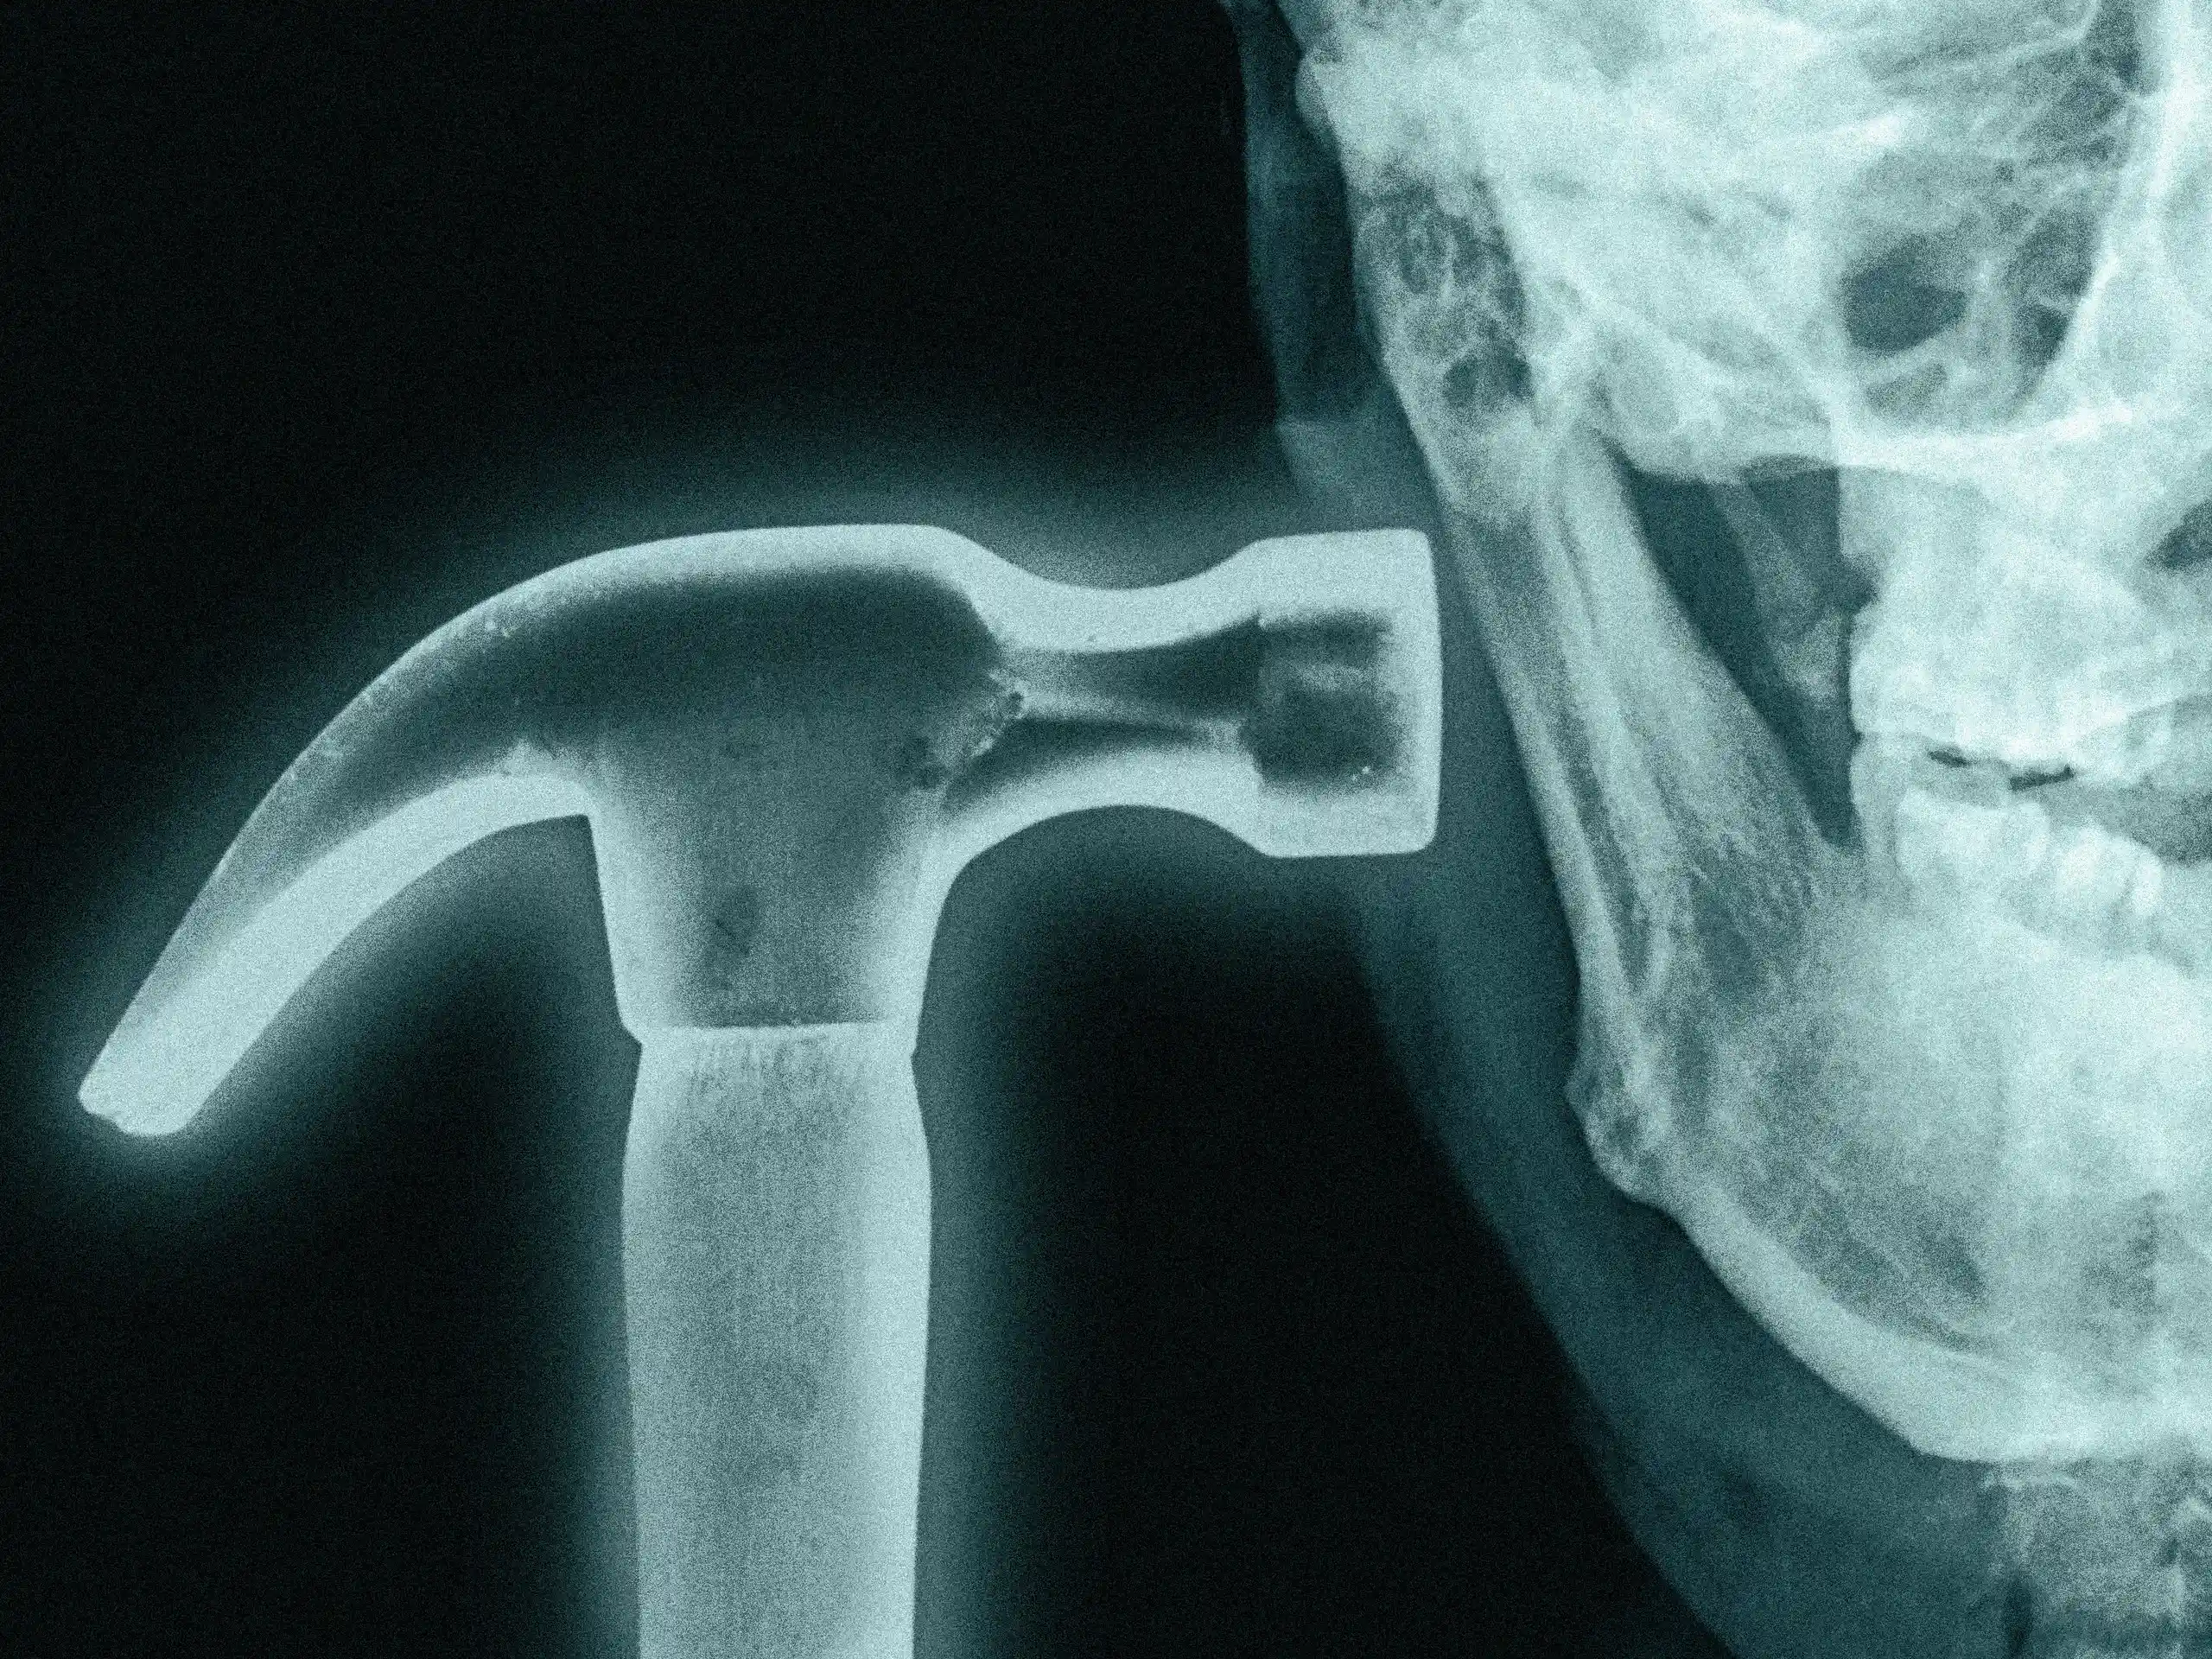

Hardmaxxing dan sisi ekstremnya

Namun gerakan ini juga memiliki sisi yang lebih radikal, terkadang disebut “hardmaxxing”, yang mencakup operasi kosmetik, implan rahang, transplantasi rambut, penggunaan steroid, dan bahkan prosedur pemanjangan anggota tubuh yang dimaksudkan untuk menambah tinggi badan.

Semakin dramatis transformasinya, semakin banyak perhatian yang cenderung ditariknya secara daring.

Seorang streamer internet kontroversial yang dikenal sebagai Clavicular telah menjadi salah satu tokoh paling terlihat yang terkait dengan tren ini. Video-videonya mendokumentasikan upaya yang semakin ekstrem untuk mengubah penampilannya, mulai dari bereksperimen dengan testosteron dan steroid hingga memukul wajahnya sendiri dengan palu dengan keyakinan bahwa benturan berulang dapat membentuk kembali struktur tulang.

Klip-klip tersebut beredar luas secara daring, menggambarkan bagaimana gerakan ini bersinggungan dengan ekonomi perhatian yang lebih luas, di mana konten yang paling mengejutkan atau tidak konvensional seringkali menyebar paling jauh.